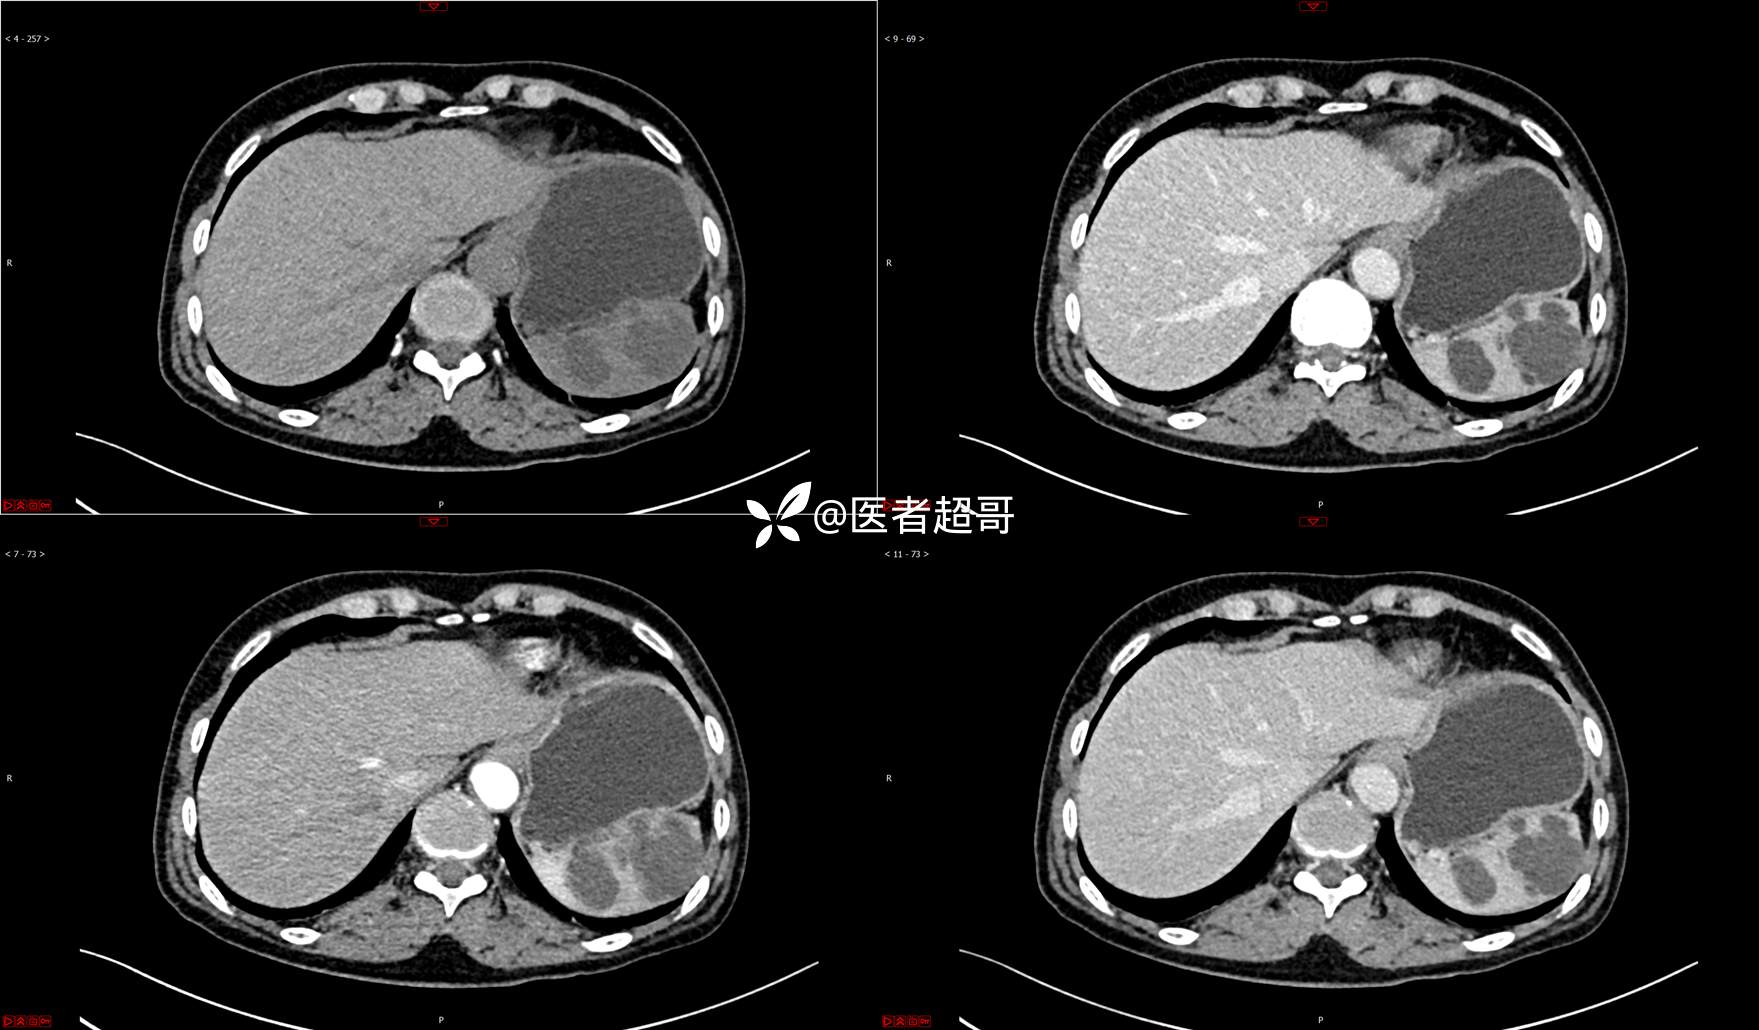

【影诊笔记739】脾脏囊性占位,查体偶发,请赏析,有病理!

主 诉:查体发现脾脏囊性占位4年。

现病史:患者4年前于人民医院查体时发现脾脏囊性占位。-04-20到我院复查,行上腹平扫+强化CT示:肝囊肿,脾脏囊实性占位,囊腺瘤?当时无明显症状,未行任何治疗。4个月前无明显原因及诱因开始偶尔出现左上腹疼痛,为隐痛,伴腰部放射痛,无腹胀、腹泻,无恶心、呕吐,无发热、畏寒、全身乏力,无胸痛、胸闷等其它不适。在外未行特殊治疗,今为求进一步诊治来我院就诊,行腹部彩超(肝、胆、胰、脾、肾)示:脾脏房囊性肿物。门诊以“脾占位性病变”收入院。发病以来,患者神志清楚,精神可,饮食可,睡眠欠佳,大小便正常,近期体重无明显变化。